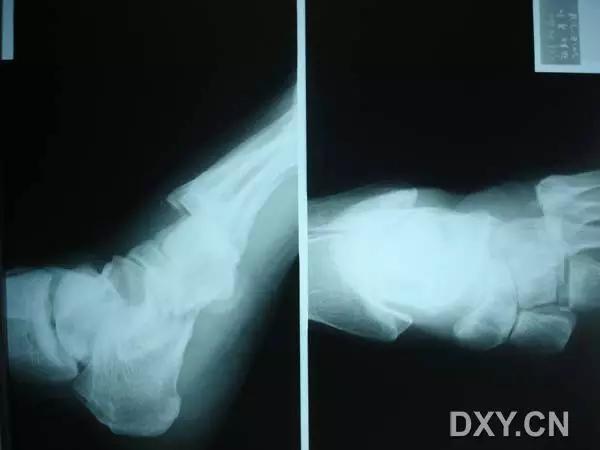

14.第五跖骨骨折

第五跖骨基底部骨折的不同类型:Stress 骨折;Jones 骨折:第五跖骨基底部以远 1 英寸内的骨折称为 Jones 骨折; Avulsion 骨折。

(来源:Radiopaedia)

Stress 骨折(来源:OrthoInfo-AAOS)

Jones 骨折正位片(来源:Radiopaedia)

Jones 骨折斜位片(来源:Radiopaedia)

第五跖骨骨折还有 dancer’s fracture。

dancer’s fracture 正位片(来源:footEducation)

dancer’s fracture 侧位片(来源:footEducation)